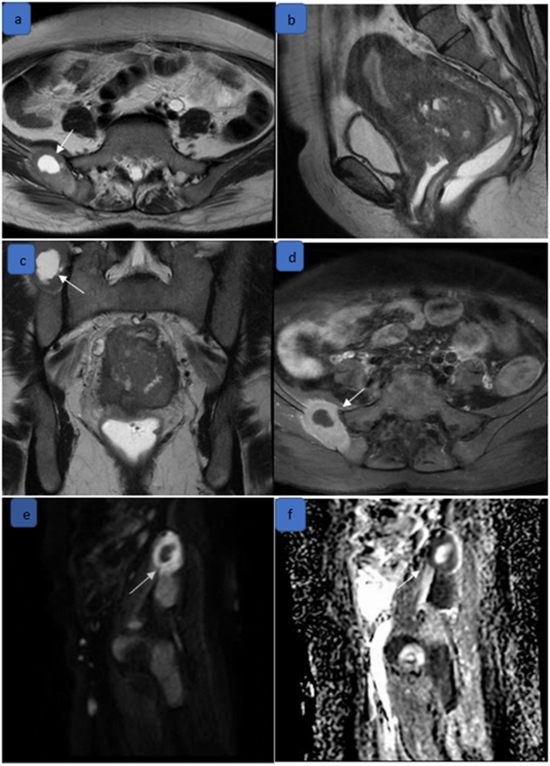

Material and methods: In this retrospective cross-sectional study, pelvic MRIs of 128 patients with cervical cancer were evaluated. For all patients, staging was performed by two independent radiologists according to the 2018 FIGO Staging Classification, first based on modified protocol and then based on full protocol MRI. Inter-modality agreement was evaluated by Cohen's kappa, intraclass correlation coefficient (ICC), and concordance correlation coefficient (CCC).

Results: There was very good agreement between the modified and full protocols in preoperative staging of cervical cancer (weighted kappa: 0.967) with a low number of discrepancies. There was also a high level of agreement between two modalities in the determination of parametrium, pelvic side wall, bladder, intestine, uterine, and lymph node involvements, as well as hydronephrosis and vascular encasement. Tumors at stage I had significantly higher ADC values compared to higher-stage tumors (p-value: 0.003).

Conclusion: Based on our study, modified MRI (including T2WI and DWI images) had substantial agreement with full protocol MRI in preoperative cervical cancer staging, suggesting its potential as a reliable contrast-free alternative for clinical practice.